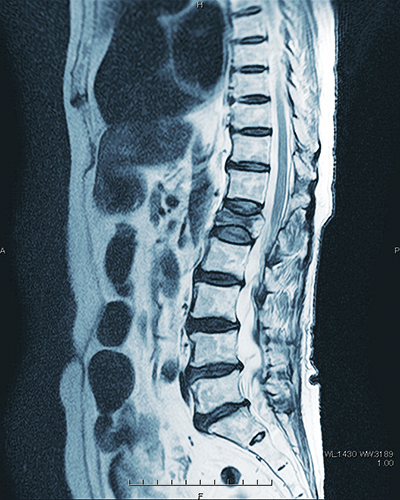

脊椎のX線写真。黒く映っている下から5つ目の第1腰椎が骨折部位

つぶれた第1腰椎に顆粒状の人工骨を充填。その上下の椎体をスクリューとロッドで固定し、脊椎を安定させる